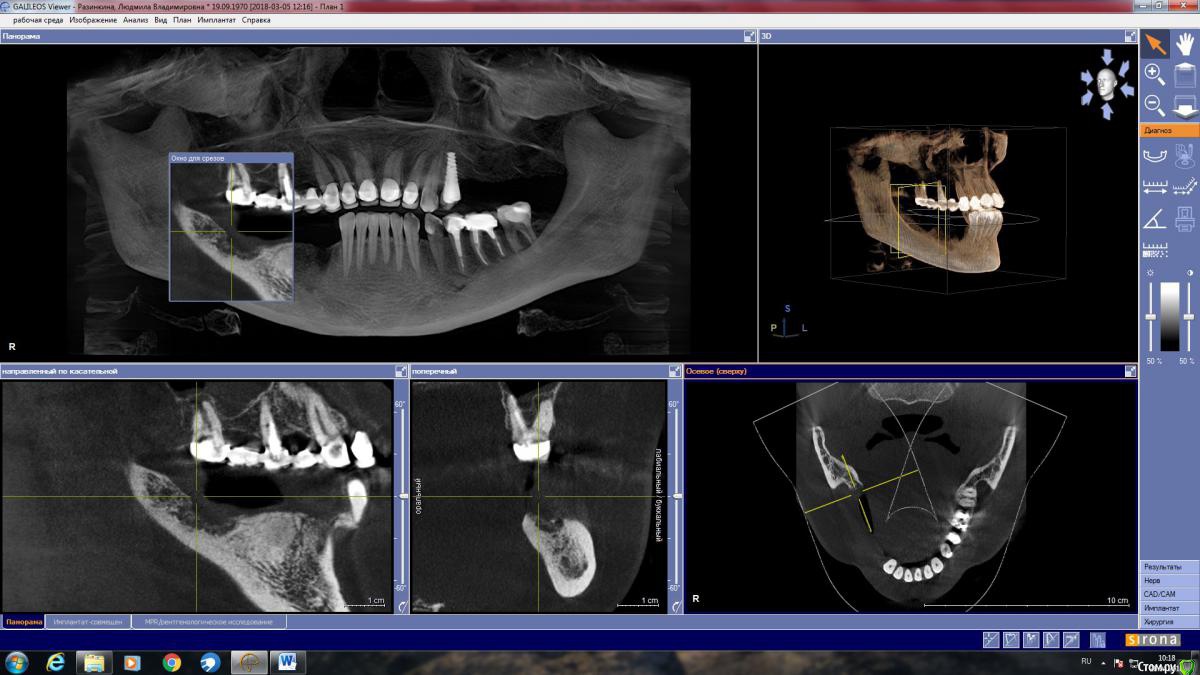

LjudmilaRaz Опубликовано 27 апреля, 2018 Поделиться Опубликовано 27 апреля, 2018 Здравствуйте! Напишите, пожалуйста, своё мнение. В первую очередь планирую имплантацию снизу справа!Обращалась на консультацию к трем врачам. Первый имплантолог предложил нарастить кость и установить четыре импланта. Врач работает только с имплантами одной фирмы (немецкие). Смутило, что полгода назад вариант был совершенно другой и еще то, что очень дорого.Второй предлагает нарастить кость и установить имплант Астра на месте удаленной в декабре четверки со смещением ближе к месту пятерки, и имплант Анкилоз на месте семерки со смещением к шестерке. То есть, накрыв мостом, получится не четыре, а три зуба.Такой же вариант, но с южно-корейскими имплантами (работаю только с ними), предложил третий имплантолог. Это относится к случаю, когда если двое говорят разное, то стоит послушать третьего ? Ссылка на комментарий

LjudmilaRaz Опубликовано 10 мая, 2018 Автор Поделиться Опубликовано 10 мая, 2018 Здравствуйте!С врачом определилась, опытный ЧЛХ стоматолог-имплантолог, еще раз сходила на консультацию. Он считает, что в моем случае более щадяще будет использование костной пластины животного происхождения, которая, становясь после определенных манипуляций пластичной, обогнет с обеих сторон в районе 4 и 5 снизу справа, где в дальнейшем планируется установка двух имплантов (плюс еще один в районе 7-ки - в итоге 3 штуки). По его мнению, ранее им планируемое расщепление в моём случае может стать по факту невозможным, из-за анатомически неблагоприятной ситуации - мало кости. Есть место (практически 2 мм) где при рассечении кость может "съесться" инструментом.Только в моей голове всё сложилось, и тут новый виток. Что думаете про такой способ костной пластики для моего случая. Ссылка на комментарий